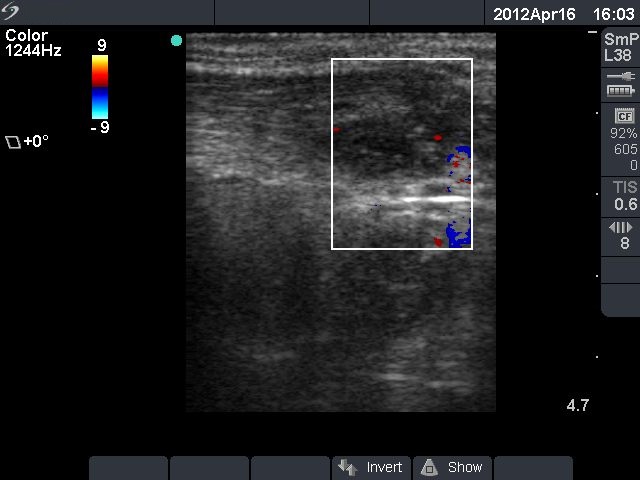

Third row: 3 days after the fourth session of ethanol treatment - the cyst became more enlarged and painful. The body temperature rose to 38.2 C, the erythrocyte sedimentation rate was 50 mm/H.

Ultrasonography: the size of the nodule was 30x25x34 mm, and another hyperechogenic lesion was found dorsal to the treated lesion.

Steroid administration resulted in a prompt amelioration of the clinical symptoms. The steroid was given for 6 weeks in a decreasing dose.